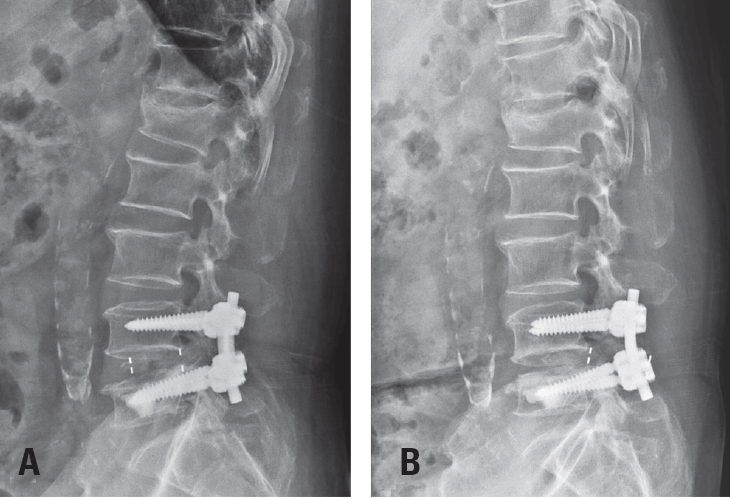

Postoperative imaging was essential for evaluating surgical outcomes. Standard radiographs and computed tomography (CT) scans were used to assess screw position and integrity. Mechanical failures—including pull-out and screw loosening—were identified by the appearance of a halo around the screw, indicating loss of fixation.10) Fig. 1 shows a typical pull-out, where the screw disengages from the vertebral body, whereas Fig. 2 demonstrates screw loosening, identified by the halo sign on CT imaging.

Fig. 1.

Postoperative radiograph demonstrating screw pull-out from the vertebral body.

Fig. 1. Postoperative radiograph demonstrating screw pull-out from the vertebral body.